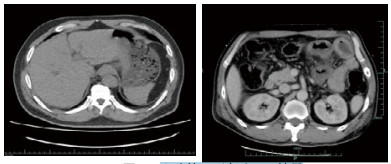

入院后在中心静脉压、有创动脉血压、每小时尿量、血气分析等严密监测下扩容补液、纠正酸中毒、亚胺培南西司他丁钠针联合利奈唑胺针抗感染、持续性血液净化纠正内环境等综合治疗后,病情逐渐好转,尿量增加,酸中毒纠正,肾功能恢复,血钠、血酮体降至正常,血糖控制在10 mmol/L以下。入院后第2天发现患者右上肢肢端温度低,右拇指发黑,血管超声示右上肢肱动脉远心端管腔闭塞,食道超声提示主动脉瓣近无冠瓣基底部可见4 mm×4 mm中等回声。入院第3天复查CT示肠系膜上静脉及门静脉积气消失(图 2)。入院第4天血培养回报:左侧外周为产气肠杆菌,右侧外周为草绿色链球菌,根据药敏结果调整抗菌药物为头孢曲松针联合左氧氟沙星针治疗,患者病情逐渐好转后出院。

| 图 2 入院第3天复查CT结果 |